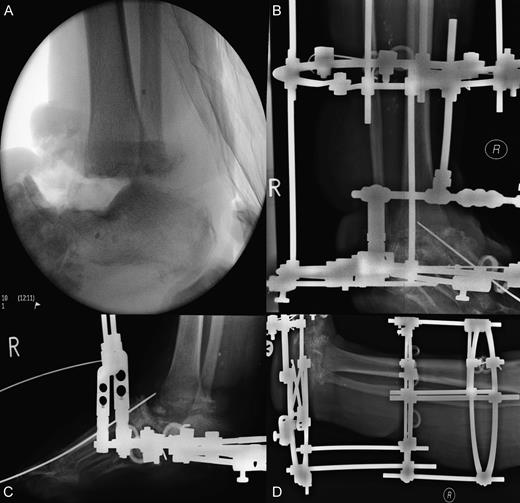

After having the external fixation for 8 months in total, it was removed when fusion was deemed adequate on computed tomography imaging (Fig. 5). She was instructed to weight bear while in a plaster of paris cast for 14 days and then a moon boot for 14 days. Two months after this, the patient was mobilizing without issues and was doing well. At 12 months, the patient stated that she is able to mobilize with any mild residual pain controlled with analgesia.

Computed tomography scans illustrating tibiocalcaneal fusion 1 year postoperatively. (A) Anterior–posterior view; (B) Lateral view.